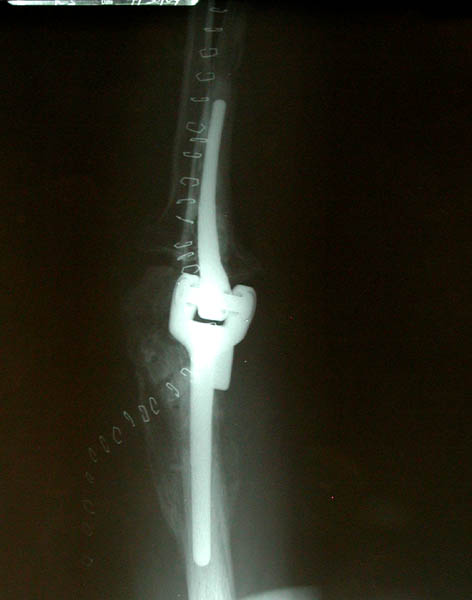

Front and side views of Marla's right elbow before her April 22nd elbow replacement surgery. The screws and plates were emplaced during the first re-construction post-trauma in December 2002. The entire infrastructure was surrounded by and interwoven with excess bone build-up, a common side effect of joint trauma coincident with head trauma. This excess bone had to be removed during her elbow replacement surgery.